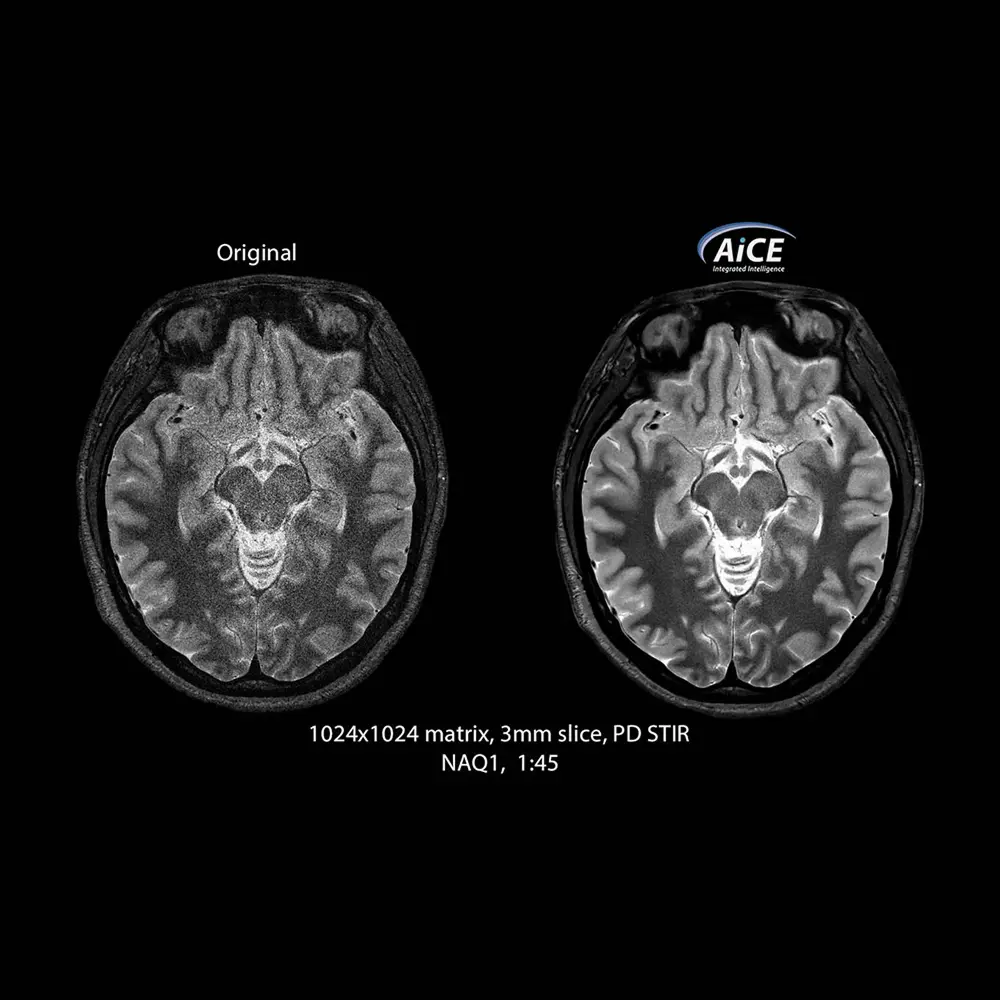

AiCE è la prima tecnologia di ricostruzione al mondo basata sul Deep Learning per la Risonanza Magnetica. È un’unità di ricostruzione opzionale nei sistemi Canon che rimuove in modo intelligente il rumore dalle immagini RM generando un elevato rapporto segnale-rumore e migliorando pertanto la risoluzione anatomica e spaziale. Un algoritmo basato sul Deep Learning riduce il rumore termico generato sull’immagine grazie ad una Rete Neurale di tipo Convolutivo (Deep Convolutional Neural Network, DCNN). La rete neurale è stata precedentemente addestrata a riprodurre immagini ad alta qualità, ottenute ad esempio con un elevato numero di medie, avendo in ingresso le stesse immagini ma caratterizzate da una forte presenza di rumore. In tal modo, AiCE è in grado di ripristinare un alto rapporto S/R in immagini MR acquisite con rapporti S/N bassi (ad esempio acquisite con alti fattori di accelerazione e/o a elevata risoluzione spaziale).